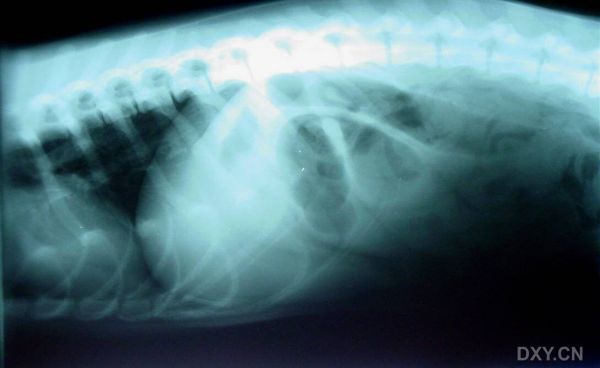

小肠管腔充气扩张

基本资料:车祸,后躯不能站立

X片如下:正位图(由于我没有X光机,片子在人医那照的,相机不好,照的较模糊,但能看见病变部位)大家描述出病变部位和治疗方案